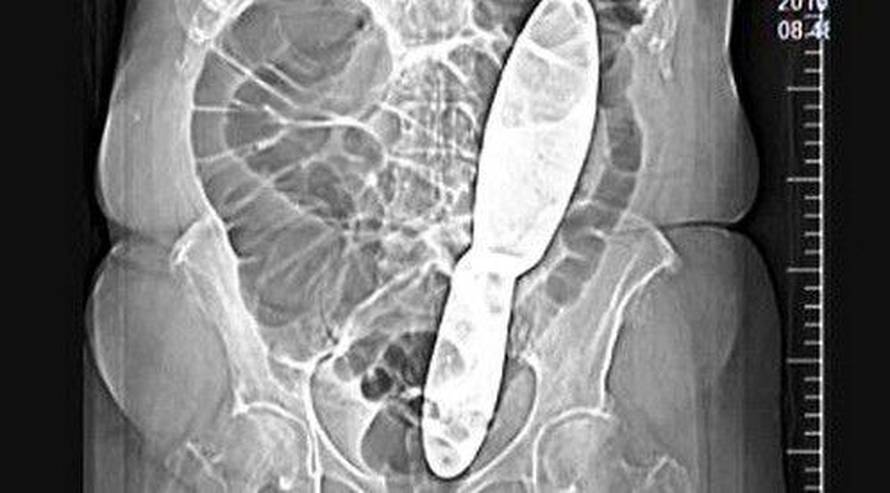

Ginekolozi su prije pet mjeseci operirali Zdenku Kopečkovu. Zaboravili su u njezinom abdomenu instrument dug 28 cm. Žena je trpila jake bolove